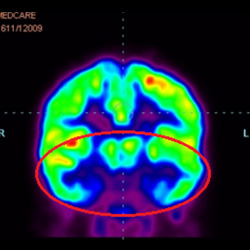

細胞治療前PET CT掃描顯示神經(jīng)組織中的藍/黑色區域,表明腦癱引起的大腦損傷。

細胞治療后,藍色和黑色區域減少,并且看到更活躍的區域。這表明損傷減少并改善了大腦功能。